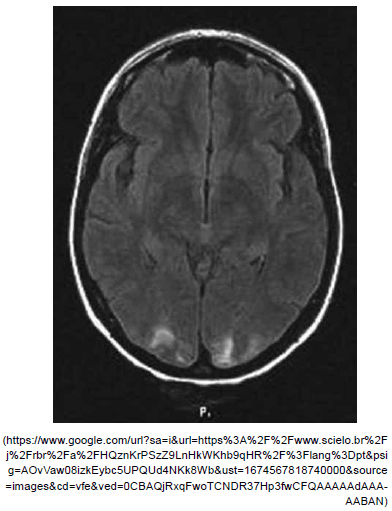

Paciente masculino, 26 anos, admitido com crises convulsivas generalizadas de início há dois dias. Tomografia de crânio a seguir. Assinale a alternativa correta quanto ao diagnóstico mais provável nesse caso.

Provas